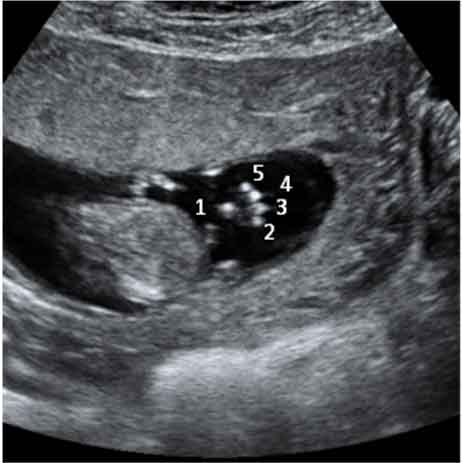

Detalle de los dedos de una mano de un feto de 12 semanas

Este bebé de 12 semanas de gestación, pone su mano en el campo de visión del ecógrafo. Por eso el especialista, comenta que "en condiciones favorables, como en este caso, pueden individualizarse los dedos". Efectivamente, podemos contar los cinco dedos del bebé, que se señalan con números en la imagen.